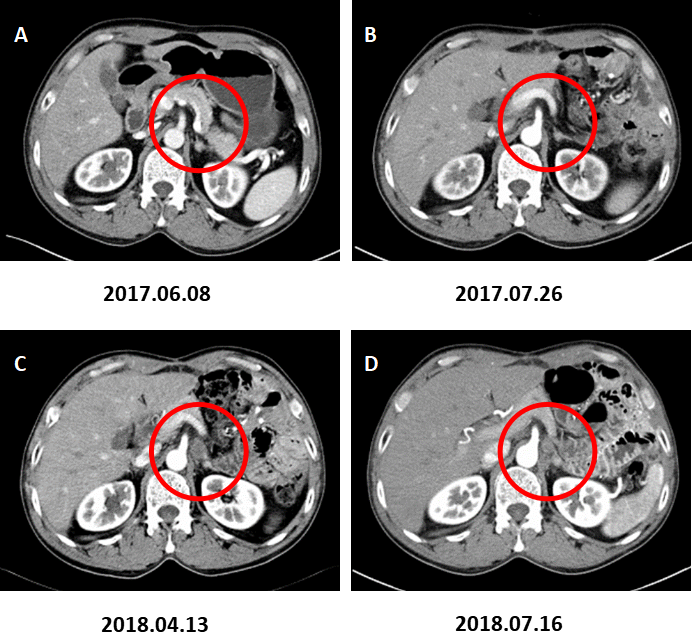

全腹部CT增强扫描(2017.06.08):胃底壁增厚,增强后均匀中度强化,大小范围约20*19mm;伴膈下区一枚肿大淋巴结,大小约10.4*15.4mm。左侧肾上腺增生首先考虑;后腹膜多发小淋巴结。

图1. 代表性术前CT图像。

A:术前CT增强(2017.06.08)示胃底部病灶及膈下淋巴结肿大;B:左侧肾上腺增生首先考虑;后腹膜多发小淋巴结。

图2. 代表性CT图片提示膈下新发淋巴结转移。

A:术前CT增强(2017.06.08)示膈下淋巴结肿大;B:术后CT增强复查(2017.07.26)示膈下未见肿大淋巴结;C、D:术后CT增强复查(2018.04.13)示左侧膈肌后下方2枚新发淋巴结转移。

图3. 膈下淋巴结转移。

A:术前CT增强(2017.06.08)B:术后CT增强复查(2017.07.26)示膈肌脚处未见肿大淋巴结;C:术后CT增强复查(2018.04.13)示左侧膈肌脚处新发肿大淋巴结。D:术后CT增强复查(2018.07.16)示左侧膈肌脚处肿大淋巴结与C相仿。

图4. 左肾上腺转移。

A:术前CT增强(2017.06.08)、B:术后CT增强(2017.07.26)、C:术后CT增强(2018.04.13)示左肾上腺增粗,增生考虑。D:术后CT增强复查(2018.07.16)示左肾上腺结节,约2.8×1.8cm,增强后不均匀强化,转移考虑。

图5. 腹膜后淋巴结转移。

A:术前CT增强(2017.06.08)B:术后CT增强(2017.07.26)、C:术后CT增强(2018.04.13)示腹膜后小淋巴结。D:术后CT增强复查(2018.07.16)示腹膜后多发肿大淋巴结,转移考虑。

图6. 肝脏多发转移。

术前CT增强A(2017.06.08),术后CT增强B(2017.07.26)、C(2018.04.13)未见肝脏转移。D:术后CT增强复查(2018.07.16)示肝脏多发转移灶。